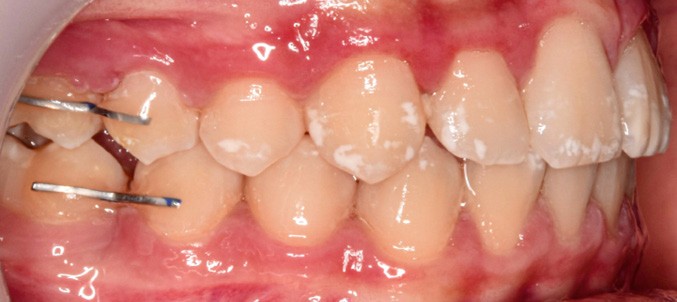

L’examen clinique montre une MIH sévère sur 16, 26, 36 et 46, et modérée sur 11 et 21.

Sur le plan alvéolo-dentaire (fig. 1b) :

- Classe II subdivision gauche avec déviation du point inter-incisif mandibulaire à gauche ;

- occlusion inversée entre 22 et 32 ;

- dysharmonie dento-arcade (DDA) sévère ;

- 13 en position haute retenue.